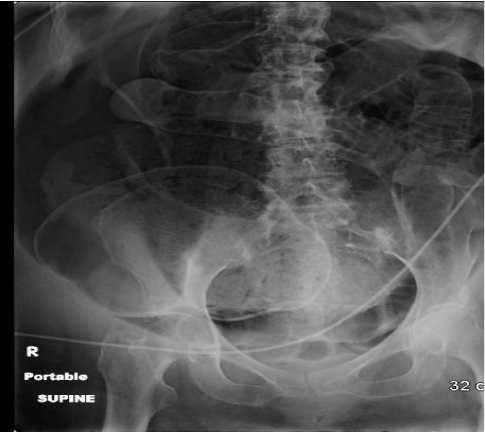

Annals of B-Pod: Abdominal Compartment Syndrome

/While compartment syndrome of the extremities is a much feared complication - what happens when you get compartment syndrome of the abdomen? Does this mean you really shouldn't trust your gut? In this article, Dr. Harty discusses through the evaluation and management of abdominal compartment syndrome in this week's issue of Annals of B-Pod.